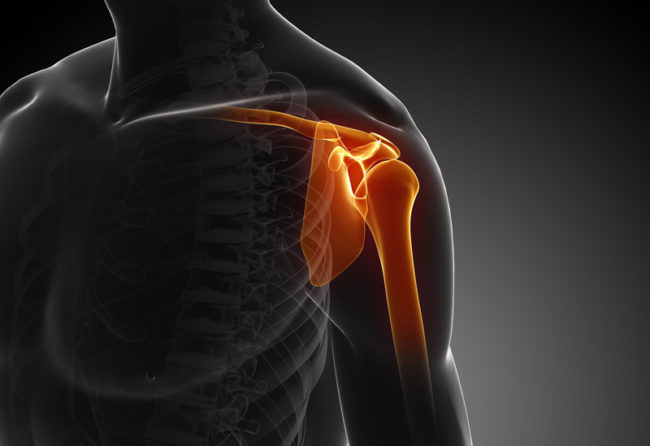

Artritele umarului

Termenul de artrita literar este folosit pentru a descrie o inflamatie intraarticulara, insa se asociaza folosirea lui cu leziunile de cartilaj articular. Astfel distrugerea cartilajului articular in interiorul articulatiei gleno-humerale cauzeaza artrita umarului. Gradul de afectare a cartilajului articular si inflamatia intraarticulara, variaza cu tipul si stadiul artritei. In stadiile avansate, cand nu mai exista…